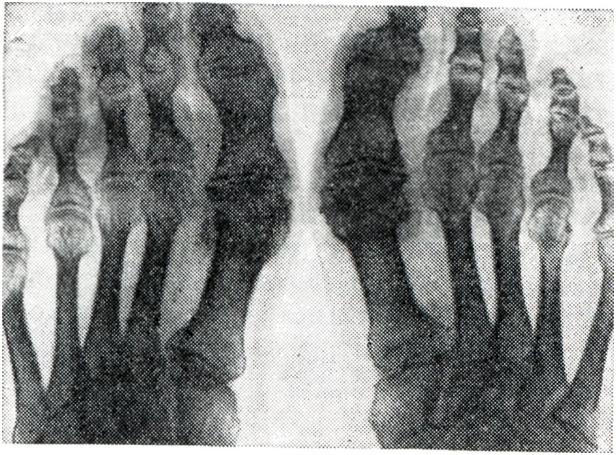

Кроме перечисленных общих клинических и рентгенологических симптомов, артрозы отдельных суставов имеют некоторые дополнительные особенности. Артроз дистальных межфаланговых суставов пальцев рук (геберденовские узелки, геберденоартроз) представляет собой одну из наиболее частых локализаций первичного артроза, обычно поражает женщин, особенно в климактерическом и постклимактерическом периодах. Геберденовские узелки (рис. 9, 10) считаются ранним проявлением первичного генетически обусловленного полиартроза, который одновременно связывают с перегрузкой дистальных межфаланговых суставов мелкой и напряженной работой. Геберденовские узелки развиваются очень медленно, бессимптомно, часто незаметно для самого больного. Лишь в поздние сроки появляются небольшие боли, обычно при смене погоды, небольшая болезненность при пальпации и образуются заметные возвышения по обеим сторонам тыльной поверхности дистальных межфаланговых суставов. На рентгенограмме отмечается сужение суставных щелей, неровность суставных поверхностей, подхрящевой склероз и боковые остеофиты. Артроз проксимальных межфаланговых суставов пальцев рук (бушаровские узелки) встречается значительно реже, чем геберденовские узелки, но по своей клинической и рентгенологической картине от последних почти не отличается. Как правило, бушаровские узелки появляются у лиц, имеющих геберденовские узелки (рис. 9). Это помогает отличить их от ревматоидного артрита, при котором очень часто поражаются проксимальные межфаланговые и пястно-фаланговые суставы раздельно или совместно. Кроме того, деформация сустава при бушаровских узелках обусловлена не утолщением мягких тканей (как при артритах), а твердыми костными разрастаниями. Артроз запястно-пястного сустава I пальца (ризартроз большого пальца) встречается примерно так же часто, как и геберденовские узелки. При этом оба поражения могут быть одновременно. Причиной ризартроза является частая микротравматизация. Клиническая и рентгенологическая картина (рис. 11) — такая же, как и при артрозе двух предшествующих локализаций. Артроз локтевого сустава наблюдается реже в связи с уменьшенной на него нагрузкой. Однако при некоторых видах труда, особенно с виброинструментами, создаются иногда условия для длительной микротравматизации этих суставов и для развития профессионального артроза (у шахтеров, кузнецов, литейщиков, каменщиков и др.), который проявляется резкими болями, усиливающимися после полного сгибания и разгибания в суставе. Вскоре наступает некоторое ограничение его подвижности. Часто отмечается грубый хруст в суставе при движениях. Кроме сужения суставной щели (рис. 12), подхрящевого остеосклероза и краевых остеофитов, часто наблюдаются суставные мыши, представляющие собой либо кусочки оторвавшегося и затем обызвествленного хряща (например, при расслаивающемся остеохондрите), либо проявление суставного хондроматоза. Артроз тазобедренных суставо в (коксартроз) является одной из наиболее частых и тяжелых форм дегенеративных заболеваний суставов. Раннее нарушение функции этих суставов, как уже указывалось, вызвано их особой анатомической структурой. Особенно велик удельный вес вторичных форм коксартрозов, обусловленных врожденными дисплазиями, вывихами и подвывихами бедра, перенесенными заболеваниями и травмами головки бедра (болезнь Пертеса, болезнь Педжета, костно-суставной туберкулез) и другими причинами. Так, по данным Сеза (S. Seze) с соавторами (1956), вторичные коксартрозы составляют 58% всех коксартрозов, 40% из них составляют коксартрозы, обусловленные врожденным подвывихом. По данным Малвина (М. D. Marvin, 1971), обследовавшего 200 больных коксартрозом, врожденные дисморфозы тазо-бедренного сустава выявлены у 65% больных артрозом. Вторичные коксартрозы чаще неодинаково поражают оба сустава или бывают односторонними. Первичные же обычно симметричны. В отличие от других локализаций артрозов, при коксартрозах наблюдается четкая корреляция между клиническими симптомами и рентгенологическими изменениями, причем иногда даже клинические симптомы появляются в первую очередь. Боли при ходьбе и хромота вначале появляются только к концу рабочего дня, позднее держатся весь день, а в тяжелых случаях настолько интенсивны, что мешают больному заснуть, иррадиируют в коленный сустав, в седалищную и паховую область. Ограничение подвижности наступает рано. Больной вынужденно держит ногу в положении флексии, аддукции и внешней ротации. Попытка разогнуть, отвести или повернуть бедро кнутри причиняет сильную боль. Для компенсации флексионной контрактуры развивается поясничный лордоз. В результате указанных деформаций нога кажется укороченной. На рентгенограмме (рис. 13) видны все характерные для артроза изменения: сужение суставной щели (по всему суставу или только в верхней его части), подхрящевой склероз (как со стороны головки бедренной кости, так и со стороны вертлужной впадины), краевые остеофиты (также в области обеих суставных поверхностей) и костные кисты (как в эпифизарной части головки бедра, так и в тазовых костях).